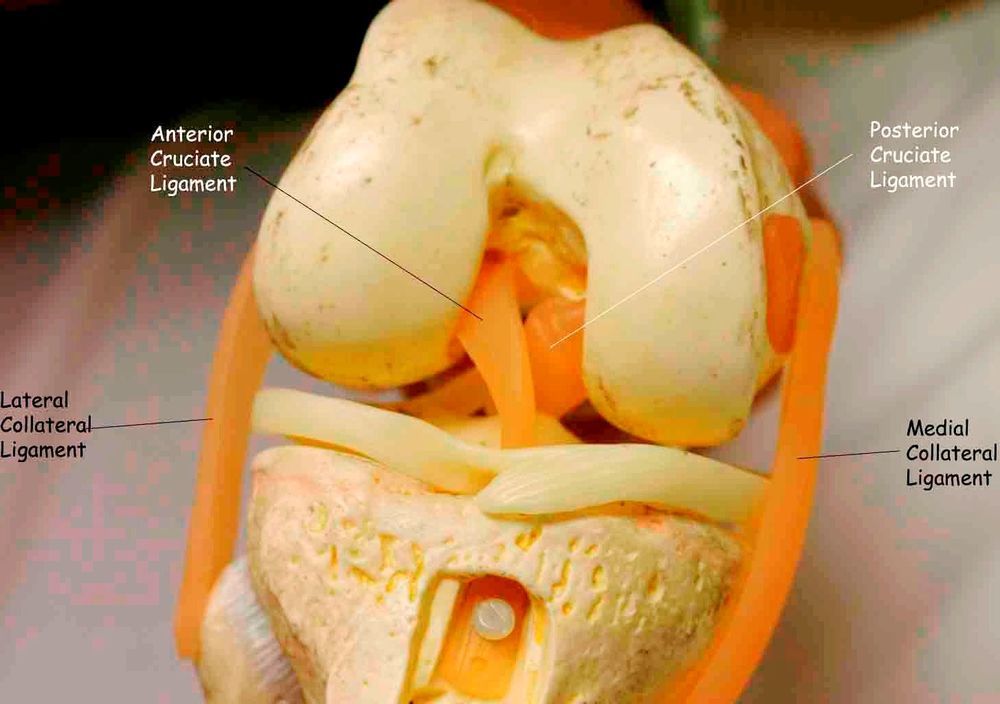

Анатомические изображения менисков и коленного сустава

Раздел: Иллюстрированные советы